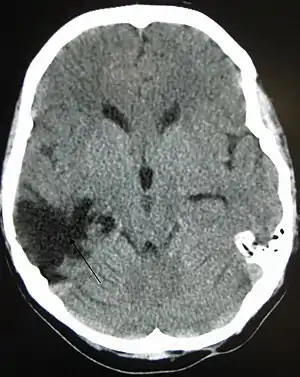

| A CT of the head years after a traumatic brain injury showing an empty space where the damage occurred, marked by the arrow |

There are several imaging techniques that can aid in diagnosing and assessing the extent of brain damage, such as computed tomography (CT) scan, magnetic resonance imaging (MRI), diffusion tensor imaging (DTI) magnetic resonance spectroscopy (MRS), positron emission tomography (PET), and single-photon emission tomography (SPECT). CT scans and MRI are the two techniques widely used and are most effective. CT scans can show brain bleeds, fractures of the skull, fluid build up in the brain that will lead to increased cranial pressure. MRI is able to better to detect smaller injuries, detect damage within the brain, diffuse axonal injury, injuries to the brainstem, posterior fossa, and subtemporal and subfrontal regions. However, patients with pacemakers, metallic implants, or other metal within their bodies are unable to have an MRI done. Typically the other imaging techniques are not used in a clinical setting because of the cost, lack of availability.[36]